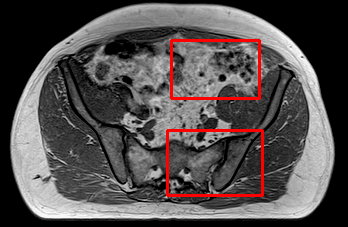

In the MRI CT translation in the Gold Atlas dataset (Fig. 8), major bones and muscles are translated faithfully. Yet, diffusion sampling leads to some inaccuracies in the outline of bones and hallucinations of the textures of inner organs. Conversely, regression sampling faithfully translates bones while still blurring the inner organs and generating artifacts. This indicates that rendering CTs is under-defined by the given MRI guidance alone.

In the quantitative analysis (Tab. 3), we found a slightly increased performance of sampling with over regression sampling in terms of PSNR and accuracy of the downstream task. As performance gains are marginal and the assessment is based on few () test cases, we still assume the performance of diffusion and regression to be similar.

Diffusion sampling YODA results in hallucinated organ shapes and textures that smoothen out and disappear when increasing the in Exp sampling or when using regression sampling. Regression sampling creates some artifacts. Note that, for all methods, the translation quality for inner organs is rather poor, whereas bone and muscle translation is reliable.

When benchmarking on the more heterogeneous and lower-quality BraTS dataset (Tab. 2, left), regression sampling of YODA achieved significantly better images than all competing methods in terms of PSNR, SSIM, and downstream glioma segmentation. Similar results were obtained in the IXI dataset (Tab. 2, right), where YODA significantly outperformed all competing methods in SSIM and PSNR. In the full-brain segmentation conducted from the synthetic images, YODA’s images were significantly better than all competing methods in at least either the Dice score or the HD. In the MRI CT task on the small pelvic dataset, regression and ExpA sampling achieved the highest SSIM, whereas the DB of Choo et al. [31] had the highest PSNR. Both, regression and ExpA sampling YODA also performed competitively in the downstream segmentation task. Note that, for all methods, the translation of inner organs was rather poor and included either texture hallucination (ResViT, I2I-Mamba, diffusion-sampling YODA) or an over-smooth image appearance (Choo et al. [31], SelfRDB, SynDiff, ExpA and regression sampling YODA, Fig. 8).